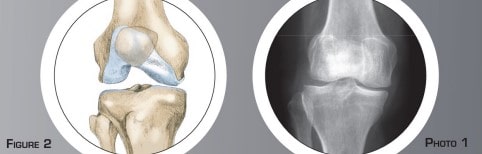

En laissant une partie intacte externe qui va réaliser une charnière osseuse (figure n°4). La correction de l’axe du membre est réalisée en ouvrant la tranche de section, jouant ainsi sur l’élasticité de la charnière externe (figure n°5). L’importance de l’ouverture est calculée en fonction de la déformation initiale et contrôlée par une radiographie per-opératoire. Une plaque est alors fixée par des vis permettant ainsi le maintien de la correction obtenue. Un substitut osseux est placé dans l’ouverture osseuse pour combler le vide et favoriser la consolidation osseuse. Dans certains cas, on lui préfère l’utilisation d’une greffe osseuse prise au niveau du bassin (figure n°6 et 7, photo n°2).